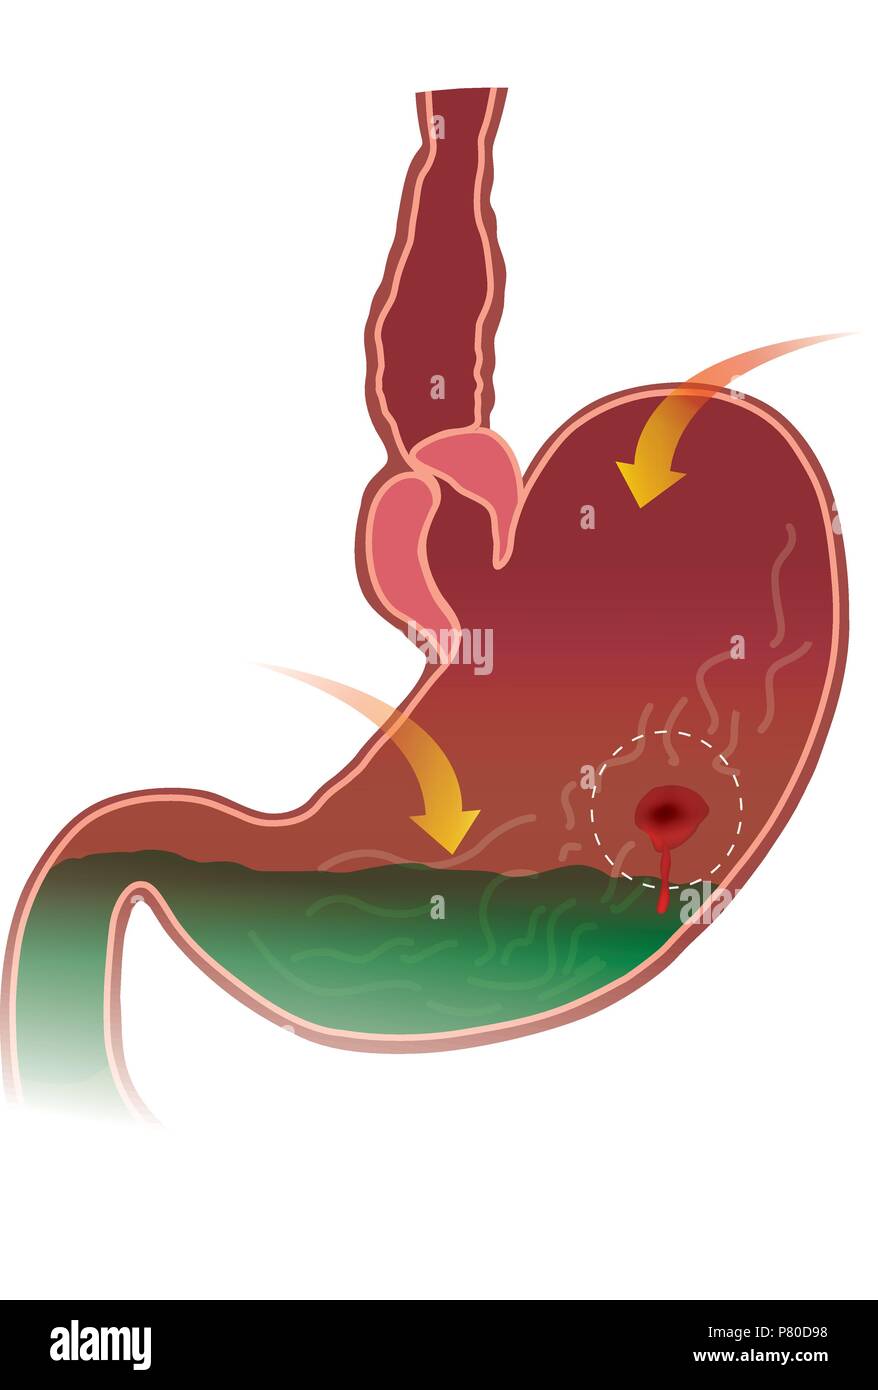

Stomaco ulcera peptica. Anatomia del corpo. Illustrazione. Illustrazione Vettorialehttps://www.alamy.it/image-license-details/?v=1https://www.alamy.it/stomaco-ulcera-peptica-anatomia-del-corpo-illustrazione-image211452116.html

Stomaco ulcera peptica. Anatomia del corpo. Illustrazione. Illustrazione Vettorialehttps://www.alamy.it/image-license-details/?v=1https://www.alamy.it/stomaco-ulcera-peptica-anatomia-del-corpo-illustrazione-image211452116.htmlRFP80D98–Stomaco ulcera peptica. Anatomia del corpo. Illustrazione.